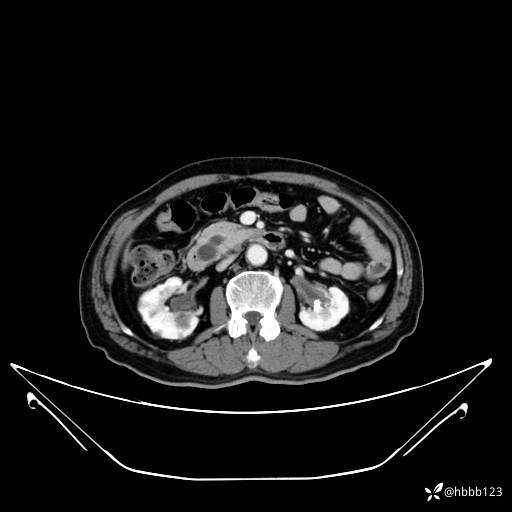

平扫: